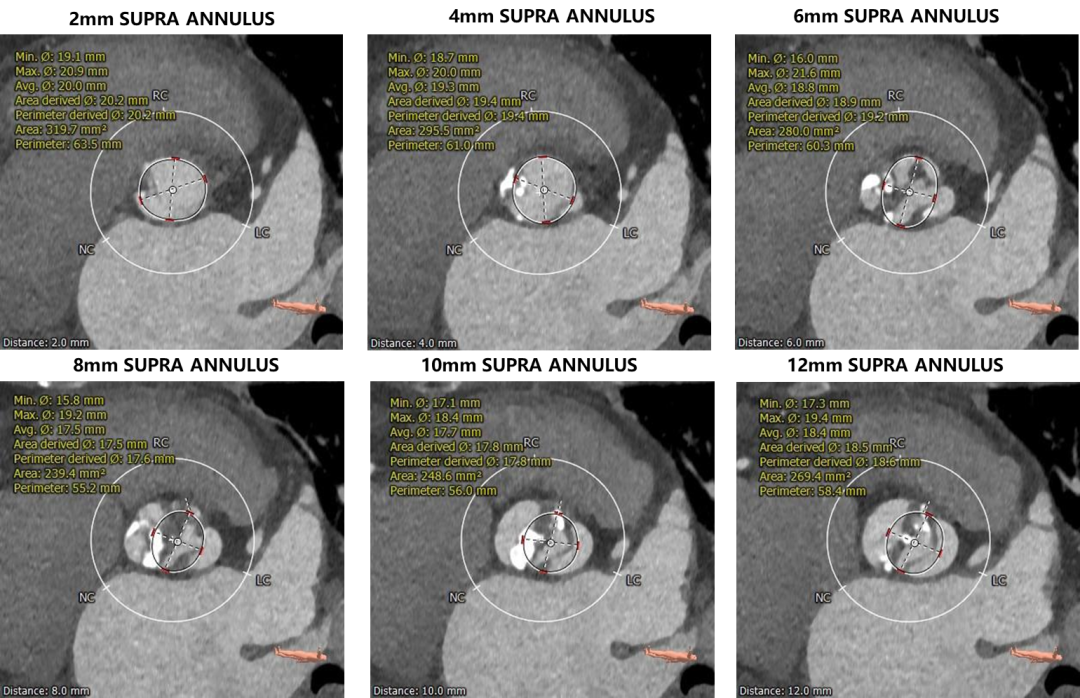

瓣上评估